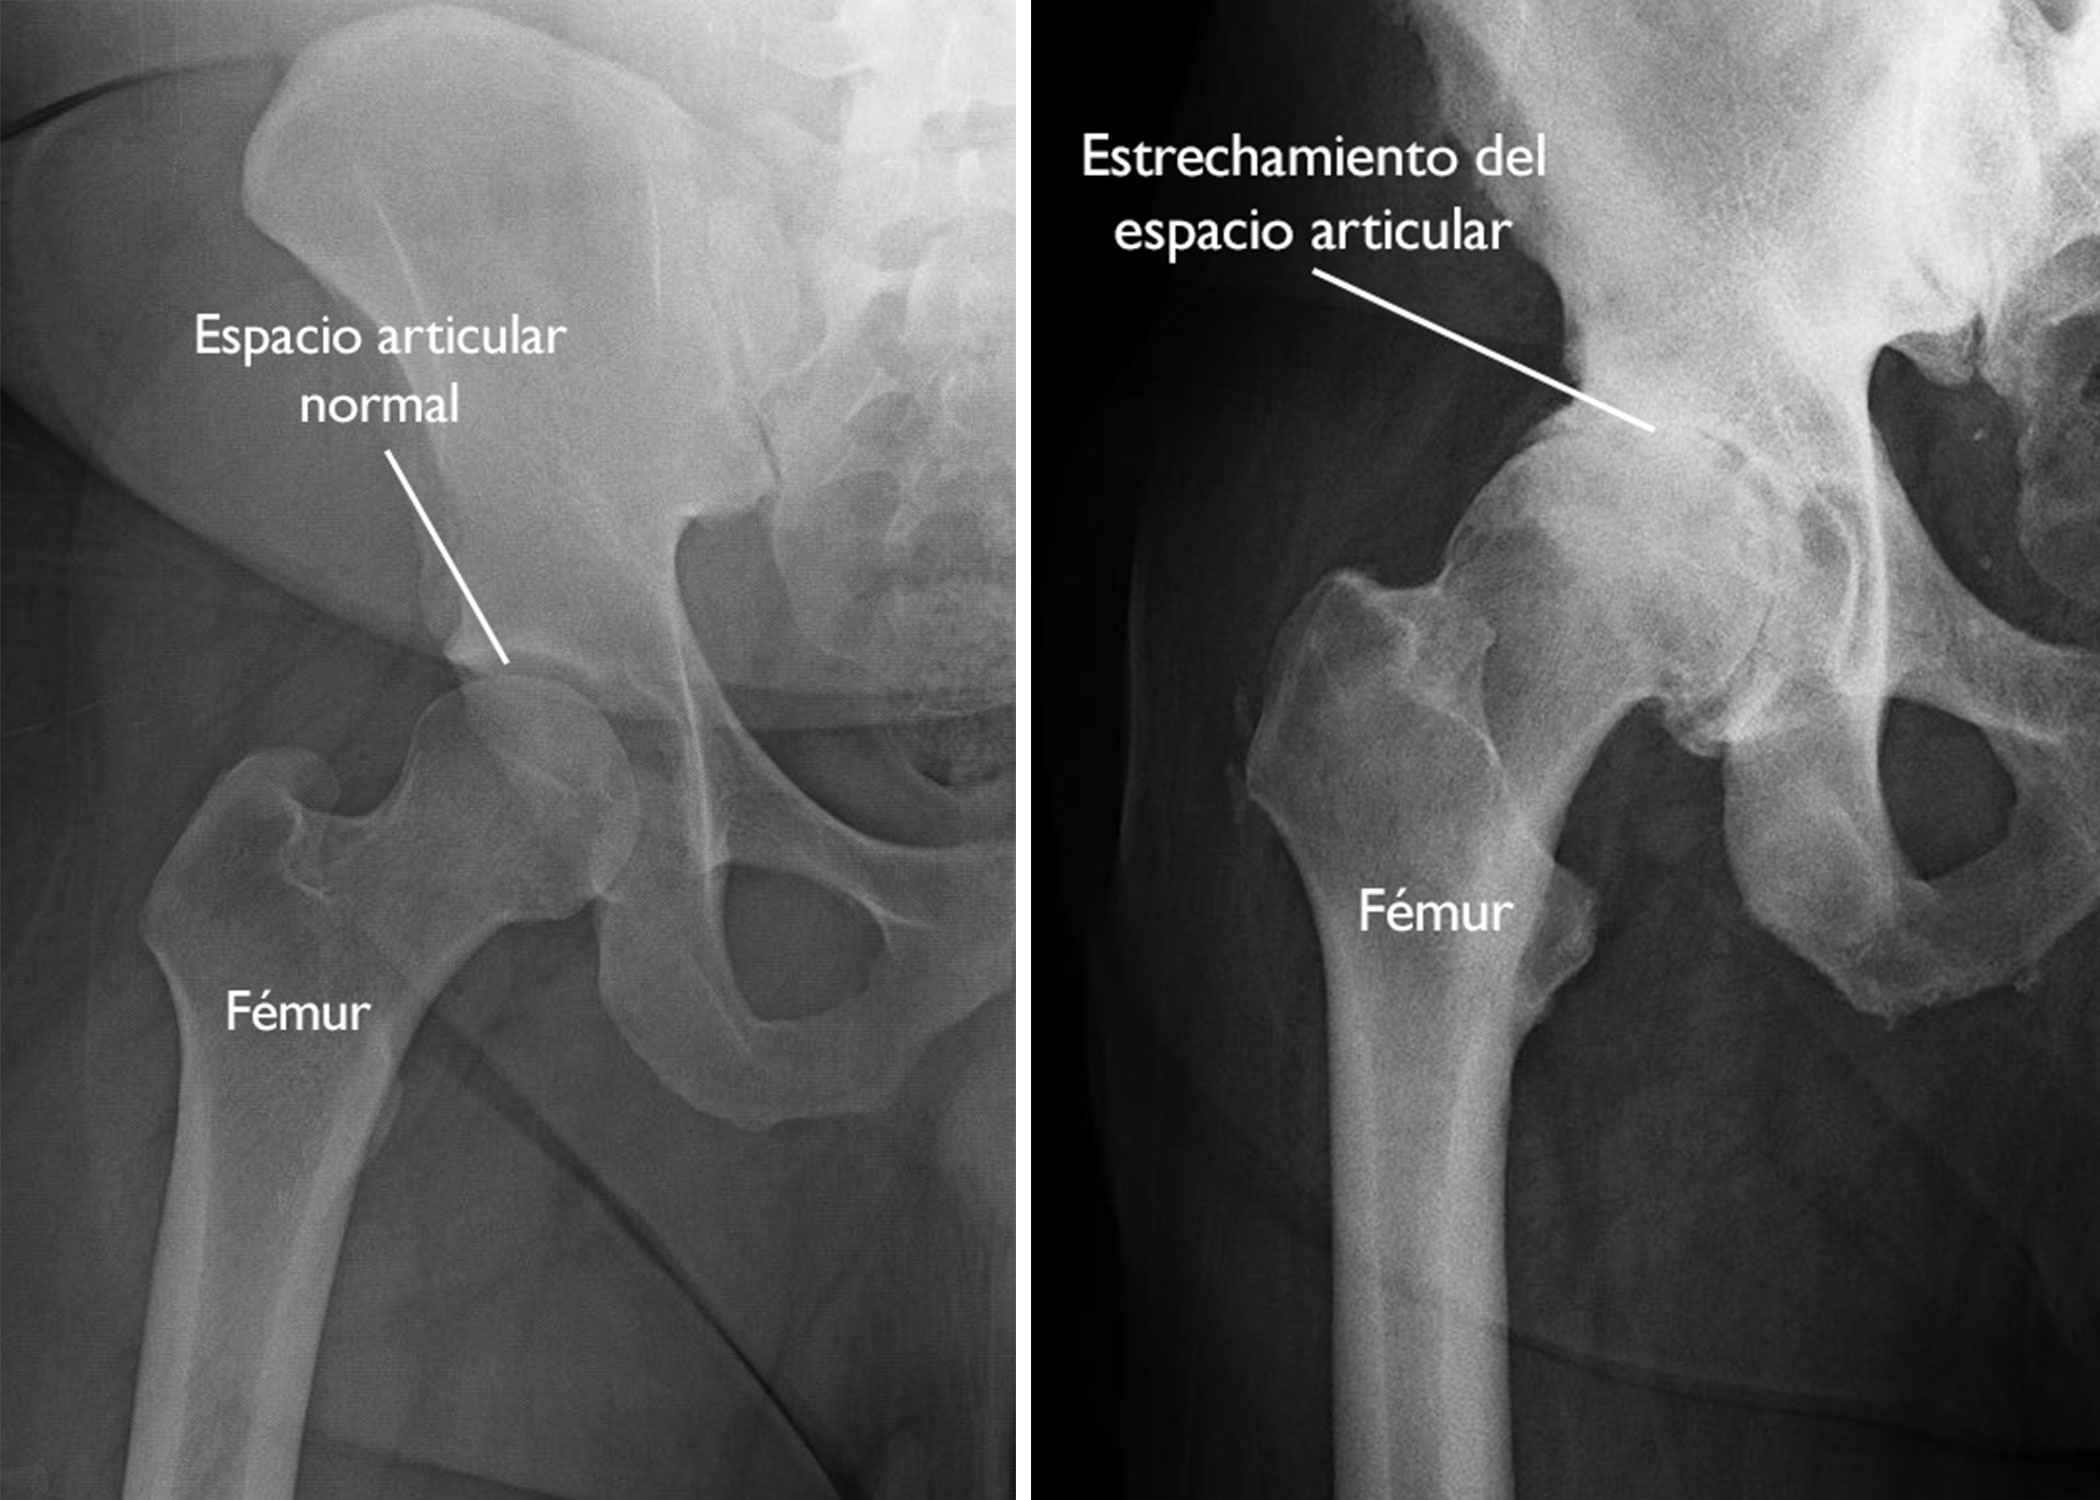

- Radiografía: Estrechamiento articular, osteofitos y esclerosis.

Cuando el cartílago se deteriora, los huesos rozan entre sí, provocando dolor, inflamación y pérdida de movilidad.